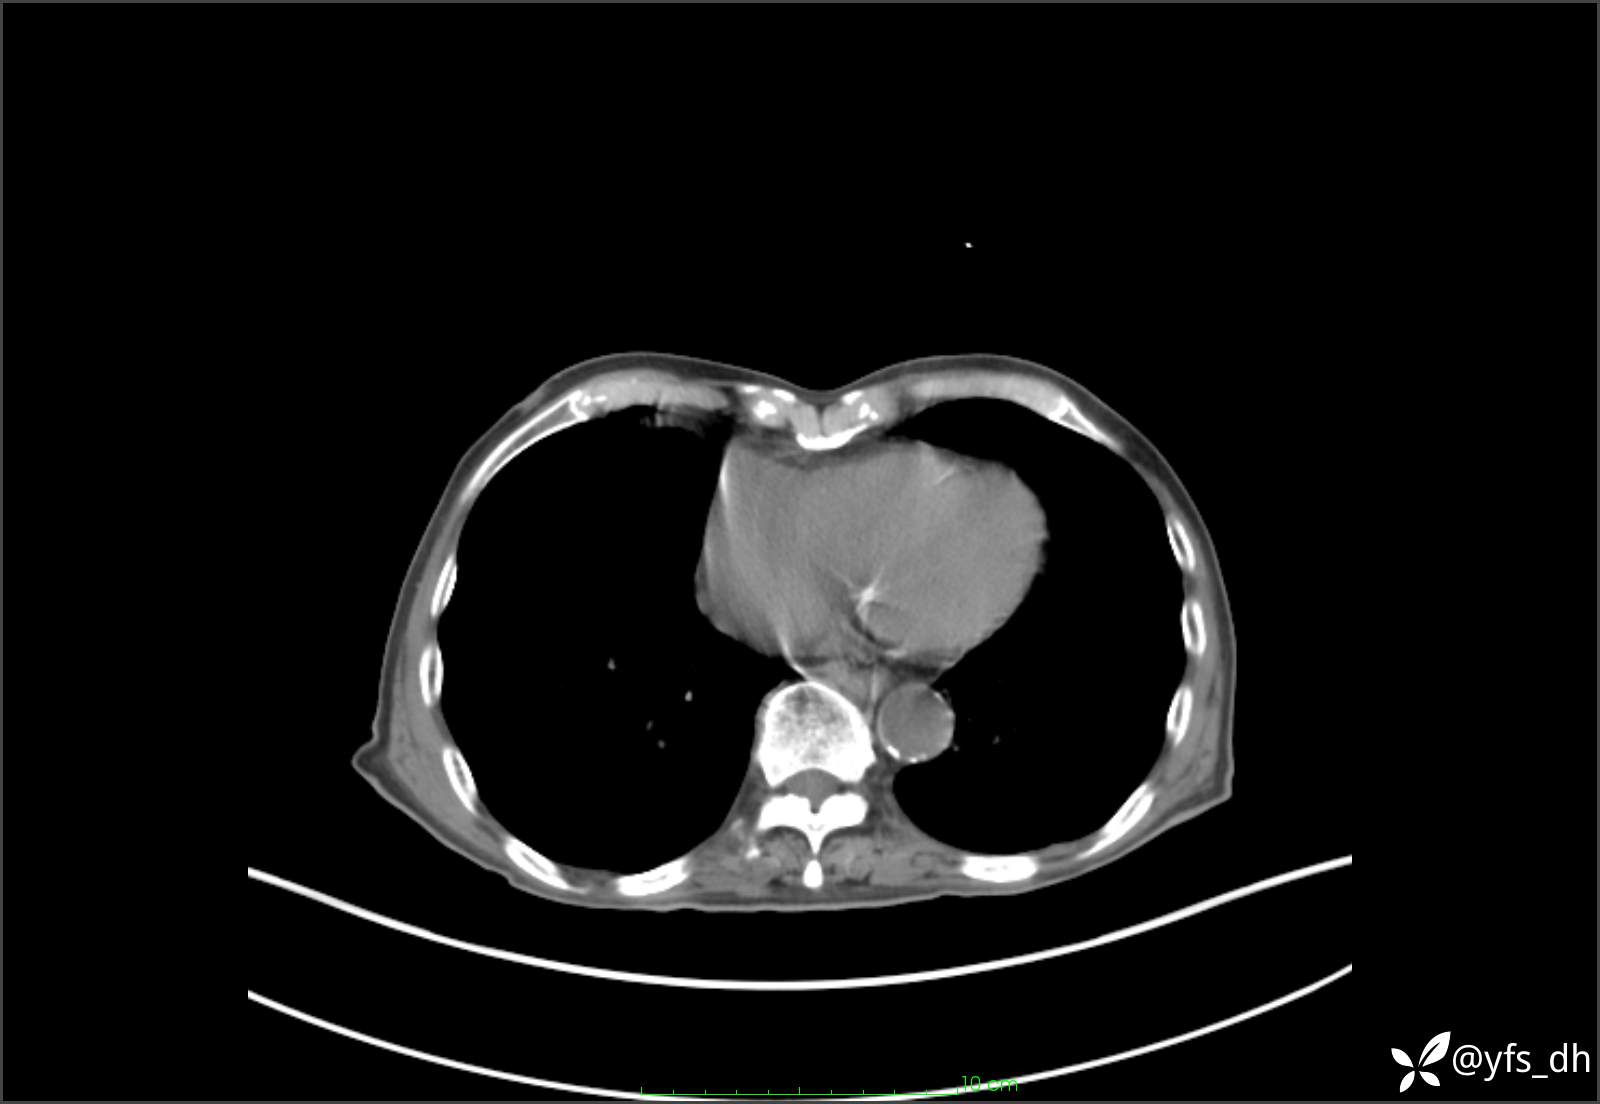

1.简要病史:患者4天前突发上腹部疼痛不适,但可以忍受。3小时前饭后突然加重,不能忍受后就诊。

2.简要手术记录:术中见腹盆腔大量肠液及粪便,乙状结肠中下段见一约3cm的破口。